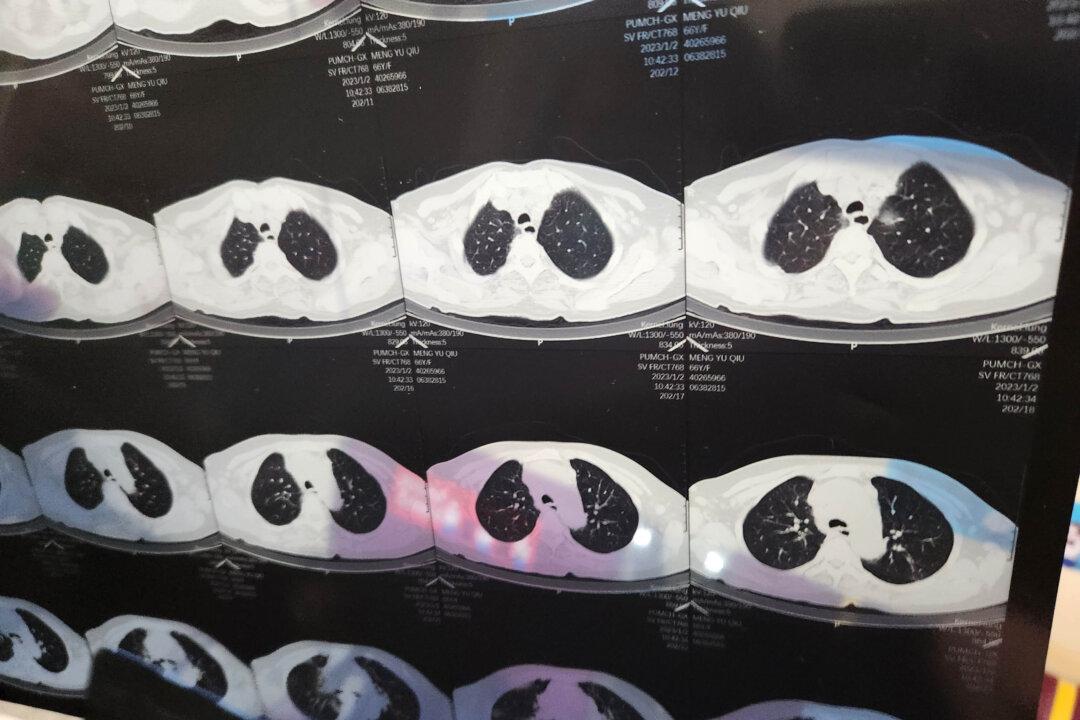

This wasn’t uncommon, after all, for someone in their 80s. The man’s mind was clear and his appetite was as good as ever. But when the family used a pulse oximeter out of caution, they found his blood oxygen level dangerously low at 88 percent, 4 percent below the threshold requiring medical attention. By the time the family got him to the hospital, his blood oxygen levels had plunged to the 60s.